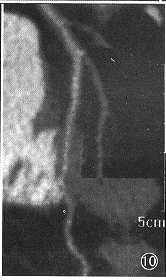

, http://www.100md.com 图10 与图8同一数据,中心线重组图像上不存在分割界面的干扰

三维显示提供的信息包括空间信息和密度信息。由于仅仅显示曲截面的展开,CPR和MAR是集中显示密度信息的方法,它们提供的空间信息在各种方法中是最少的。而对密度信息,它们显示的像素值就等于原图像的密度值,这一点没有其他方法能够做到。在体数据中,血管中心线附近的体素往往比远处的体素具有更高诊断价值。MAR贯穿中心线进行显示,就是把诊断价值高的体素优先显示。从这个意义上说,MAR在所有方法中是显示密度信息最佳的。CT和MR由于采像设备的限度,三维数据的血管边界都是模糊的,在小血管成像时给自动判定血管边界和血管径造成很大困难。例如SSD用阈值明确地分割血管边界,小血管显示得不连续(图8),狭窄经常被夸大显示。所以合理的显示是保持原数据的模糊特性,而把判断边界和管径的问题留给医生。VR和MIP能保持数据的模糊特性,但它们在投影过程中都对体素值进行了非线性运算,使血管边界和管径受调控参数的影响很大。而MAR保留了原体素值,使显示的血管边界和管径与原断层图像一致。另外,在分割兴趣区后,MIP会把分割的界面也显示出来,造成对血管边界位置的错误提示(图9)。而MAR的分割只作用于中心线的提取,并不显示出来,不会对血管边界位置造成错误提示(图10)。对于冠状动脉,诊断关心的主要是血管径而非血管结构,所以集中显示密度信息、忽略空间信息的MAR就成为首选处理方法。